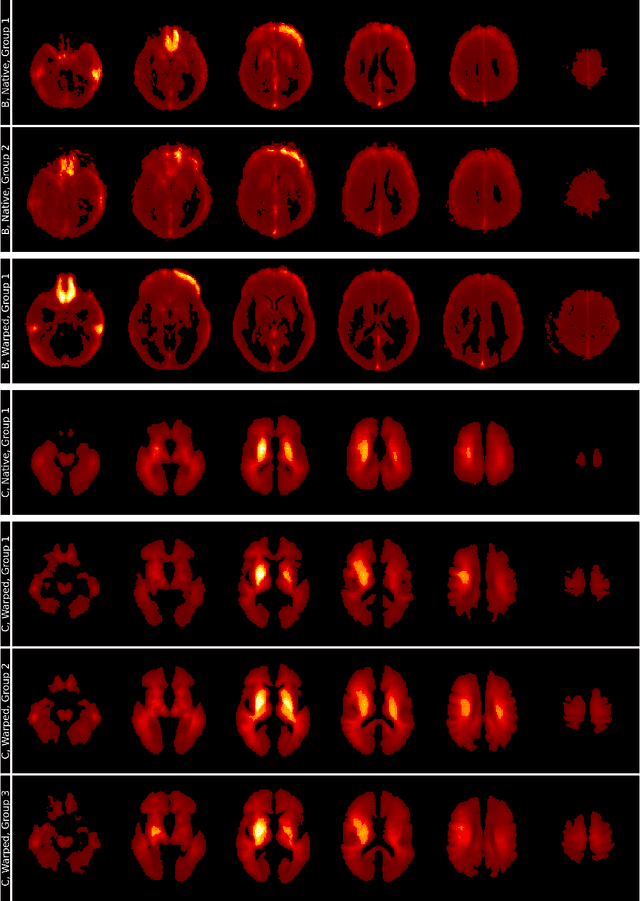

Abstract:Deep learning models have shown strong performance in classifying Alzheimer's disease (AD) from R2* maps, but their decision-making remains opaque, raising concerns about interpretability. Previous studies suggest biases in model decisions, necessitating further analysis. This study uses Layer-wise Relevance Propagation (LRP) and spectral clustering to explore classifier decision strategies across preprocessing and training configurations using R2* maps. We trained a 3D convolutional neural network on R2* maps, generating relevance heatmaps via LRP and applied spectral clustering to identify dominant patterns. t-Stochastic Neighbor Embedding (t-SNE) visualization was used to assess clustering structure. Spectral clustering revealed distinct decision patterns, with the relevance-guided model showing the clearest separation between AD and normal control (NC) cases. The t-SNE visualization confirmed that this model aligned heatmap groupings with the underlying subject groups. Our findings highlight the significant impact of preprocessing and training choices on deep learning models trained on R2* maps, even with similar performance metrics. Spectral clustering offers a structured method to identify classification strategy differences, emphasizing the importance of explainability in medical AI.

Abstract:Motivation. While recent studies show high accuracy in the classification of Alzheimer's disease using deep neural networks, the underlying learned concepts have not been investigated. Goals. To systematically identify changes in brain regions through concepts learned by the deep neural network for model validation. Approach. Using quantitative R2* maps we separated Alzheimer's patients (n=117) from normal controls (n=219) by using a convolutional neural network and systematically investigated the learned concepts using Concept Relevance Propagation and compared these results to a conventional region of interest-based analysis. Results. In line with established histological findings and the region of interest-based analyses, highly relevant concepts were primarily found in and adjacent to the basal ganglia. Impact. The identification of concepts learned by deep neural networks for disease classification enables validation of the models and could potentially improve reliability.